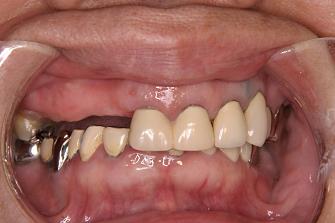

3.

バネなし入れ歯を入れた

状態です!!

* 金属のバネがないので

見栄えが良いです!

入れ歯が入っているとは

気がつかれにくいです!!